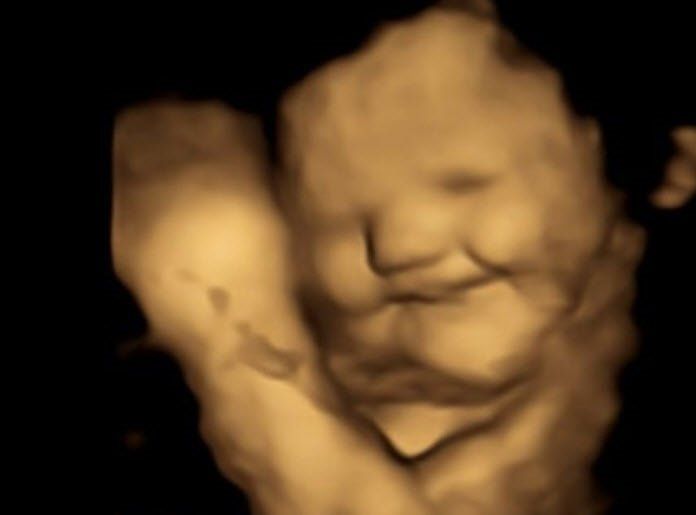

u003cbu003eANNE KARNINDA TAT ALABİLİYORLARu003c/bu003eDaha önceki çalışmalar, amniyotik sıvının solunması ve yutulması yoluyla bebeklerin tat aldığını ve kokladığını ortaya koymuştu. Bu çalışmalar doğum sonrası sonuçlara dayanıyordu.Yeni yapılan araştırma ise bebeklerin doğumdan önce tatlara verdikleri tepkileri değerlendirerek anne karnında tat alıp alamadıklarını test etti.Yaşları 18 ile 40 arasında değişen 100 hamile kadın, hamileliklerinin 32'nci haftası ile 36'ncı haftası arasında dört boyutlu ultrasonla takip edildi. Kadınlara her ultrason taramasından 20 dakika önce 400 mg havuç ve 400 mg lahana kapsülü verildi; bu esnada başka bir şey yiyip içmemeleri istendi. Kontrol grubundaki bazı kadınlara ise her iki kapsül de verilmedi. Sonuçlar, düşük miktarda havuç ve lahananın anne karnındaki bebeklerin tepki vermesi için yeterli olabileceğini gösterdi.

u003cbu003eAYNI BEBEKLERİ DOĞUMDAN SONRA DA İNCELEYECEKLERu003c/bu003eÇalışmayı yürüten ekipte yer alan Burgundy Üniversitesi'nden Profesör Benoist Schaal da Bulgular, bir dizi kimyasal uyaranın annenin beslenmesinden cenin ortamına geçtiğini gösteriyor. Bunun, tat ve koku alıcılarımızın gelişimini, ilgili algı ve hafızayı anlamamız için önemli etkileri olabilir diye konuştu.Çalışmayı yürüten ekip, şimdi de aynı bebeklerin doğum sonrası beslenmelerini takip ederek, yiyeceklere verecekleri tepkinin aynı olup olmayacağını görmeye hazırlanıyor.